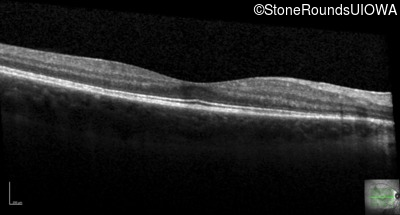

Age at visit: 14 years

This fourteen year old female has had poor vision in dim light since at least age 6.

Age at visit: 15 years

Age at visit: 16 years

Age at visit: 18 years